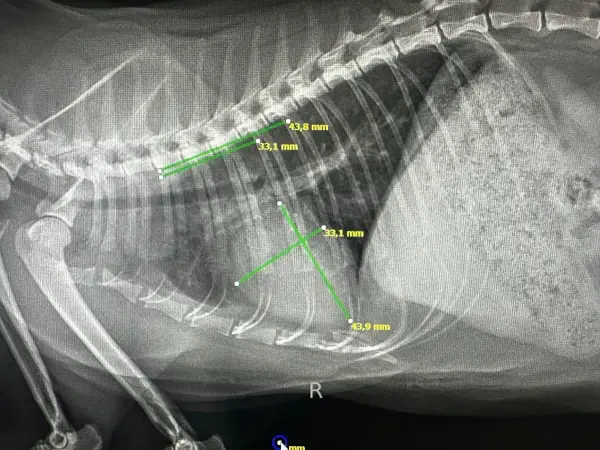

Diagnóstico por Imagen: Radiología y Ecografía

El diagnóstico por imagen es fundamental en medicina felina moderna. Muchas enfermedades solo pueden diagnosticarse mediante visualización directa de órganos internos, y la capacidad de obtener imágenes de alta calidad determina la precisión del diagnóstico.

Radiología digital: Nuestro equipo de rayos X digital proporciona imágenes de alta resolución en segundos, con una fracción de la radiación de los sistemas analógicos tradicionales. Esto es especialmente importante en gatos, donde la exposición debe minimizarse por su menor tamaño corporal.

La radiografía es insustituible para:

- Evaluación de patología respiratoria (neumonía, asma, efusión pleural)

- Diagnóstico de cardiomegalia y valoración de silueta cardíaca

- Detección de fracturas, displasias y artropatías

- Localización de cuerpos extraños radiopacos

- Evaluación de patología abdominal (obstrucción intestinal, organomegalia)

Realizamos estudios radiográficos con sedación mínima o sin sedación cuando es posible, priorizando el bienestar del paciente. En casos donde se requieren múltiples proyecciones o posiciones específicas, utilizamos sedación leve para evitar estrés y garantizar la calidad de las imágenes.